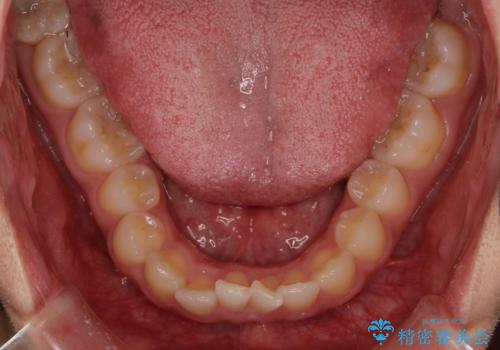

- 深い咬み合わせ(ディープバイト)と前歯のデコボコを気にして来院された患者様です。

インビザラインによる上下歯列の側方拡大と後方移動、IPR(歯と歯の間を削る)にるスペースの獲得により、デコボコとディープバイトを改善することとしました。

後方移動に際し、下顎の親知らずは2本とも抜歯することとしました。